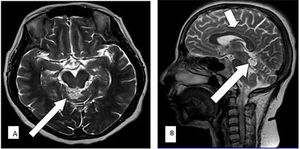

Case History: 45-year-old female with complaint of occasional headache for three years, had normal neurological and systemic exams.

Published: February 9th 2016 | Updated: